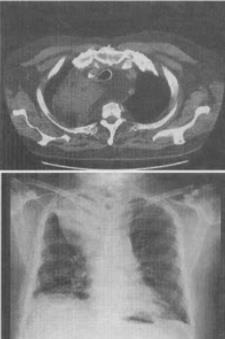

- 单项选择题1、 患者男,71岁,消瘦、咳嗽、胸痛,结合胸片和CT,最可能的诊断是()。

A、脂肪肉瘤

B、心包脂肪垫

C、脂肪蓄积症

D、胸腺脂肪瘤

E、胸腺囊肿